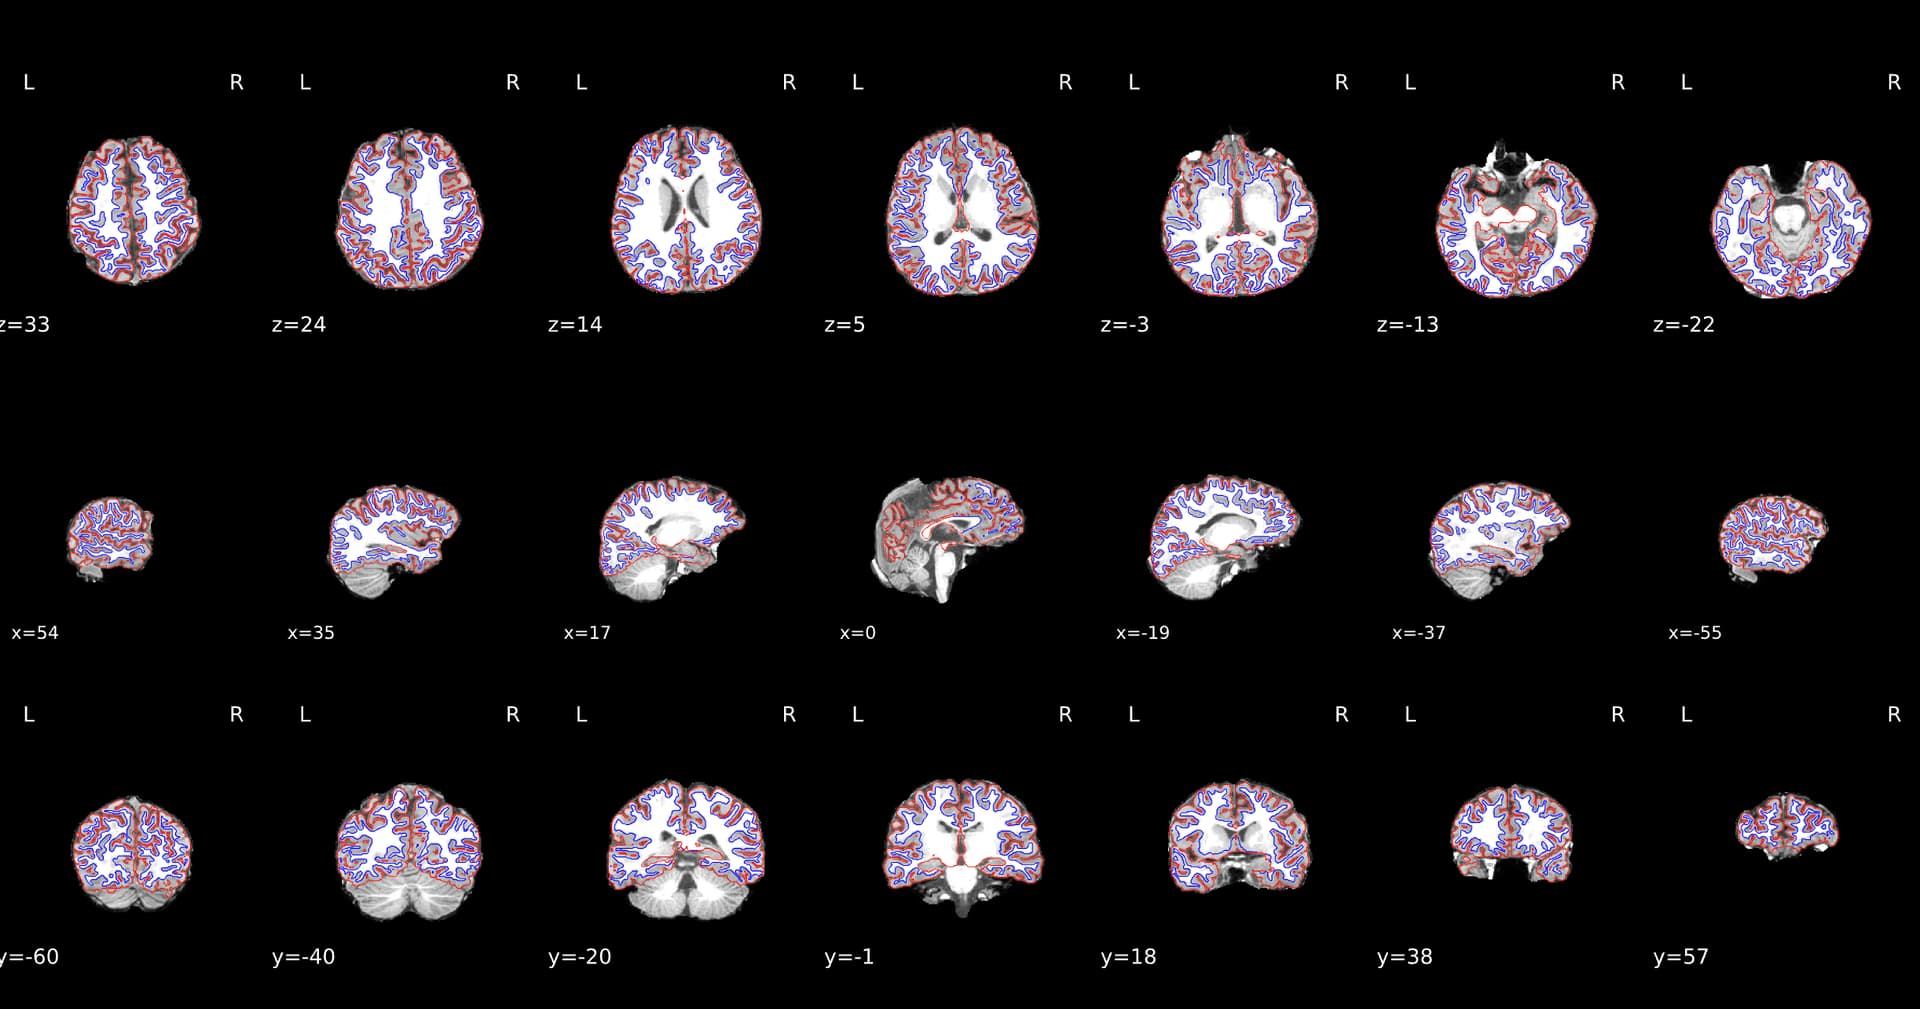

Spatial normalization

Volume-based spatial normalization to two standard spaces (MNI152NLin2009cAsym, MNI152NLin6Asym) was performed through

nonlinear registration withantsRegistration(ANTs 2.6.2),

using brain-extracted versions of both T1w reference and the T1w template.

The following templates were were selected for spatial normalization

and accessed with TemplateFlow [24.2.2, @templateflow]:

ICBM 152 Nonlinear Asymmetrical template version 2009c [@mni152nlin2009casym, RRID:SCR_008796; TemplateFlow ID: MNI152NLin2009cAsym], FSL’s MNI ICBM 152 non-linear 6th Generation Asymmetric Average Brain Stereotaxic Registration Model [@mni152nlin6asym, RRID:SCR_002823; TemplateFlow ID: MNI152NLin6Asym].